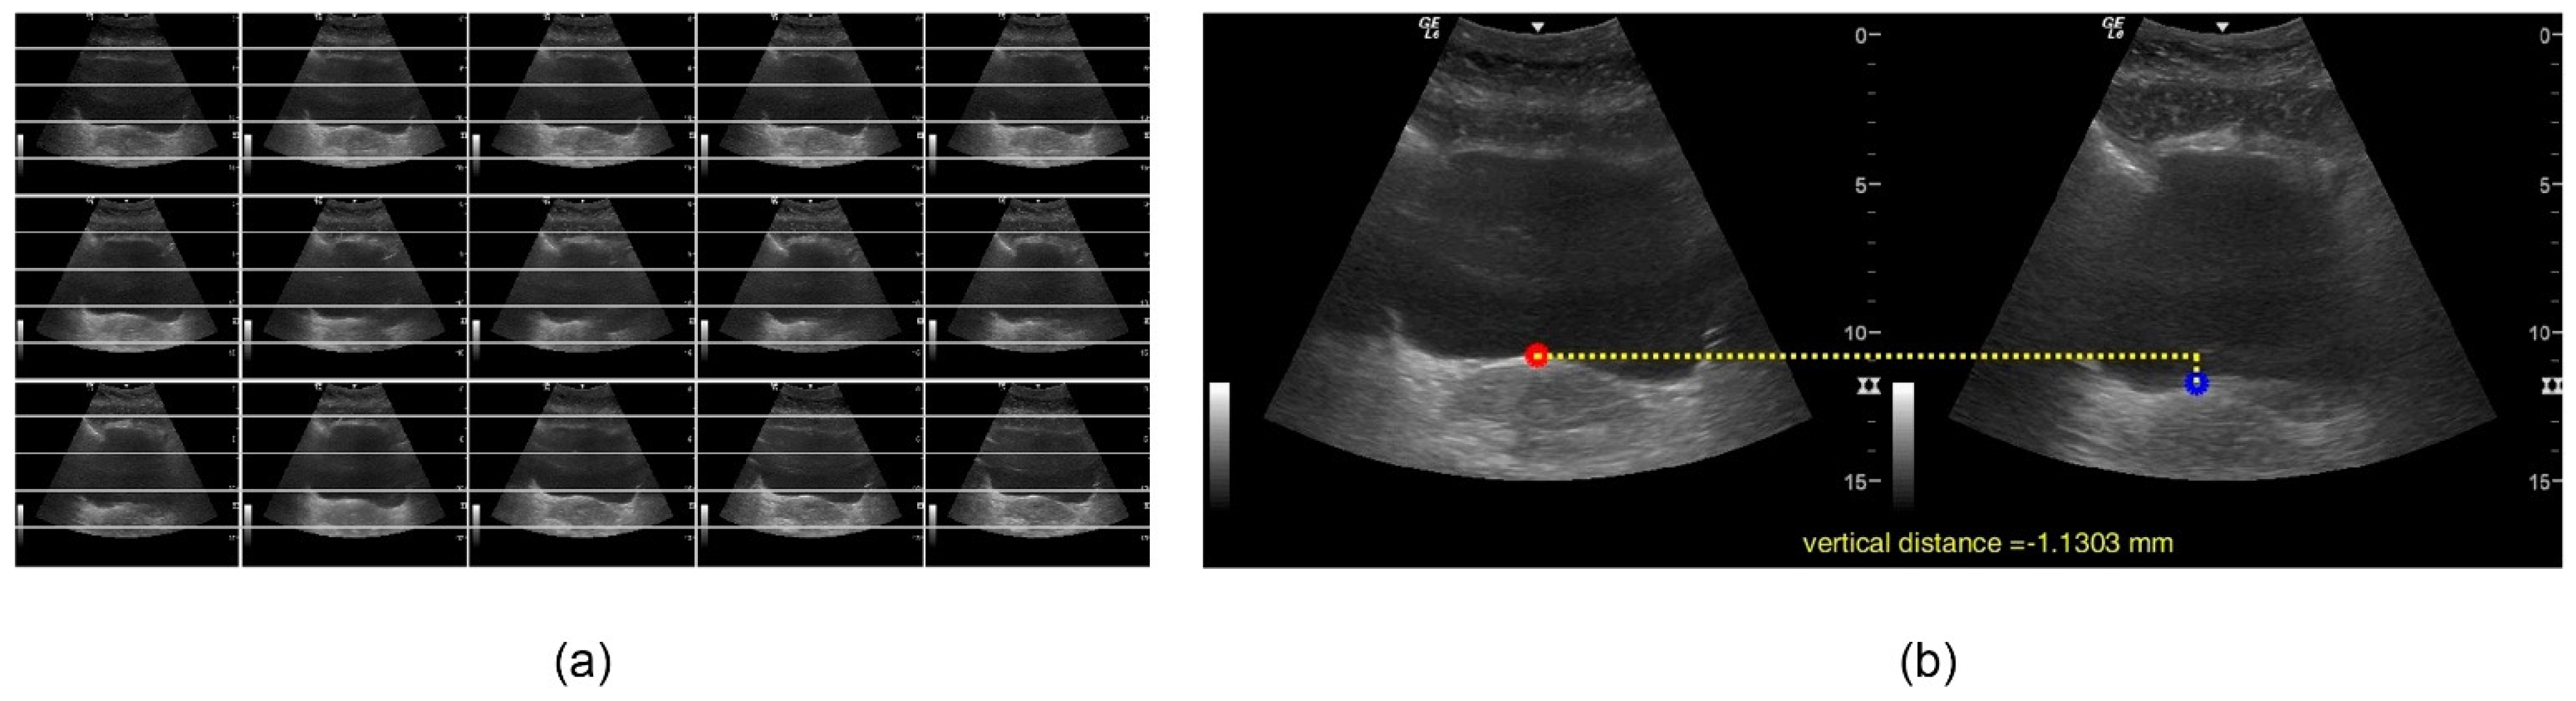

2.3. Data Processing